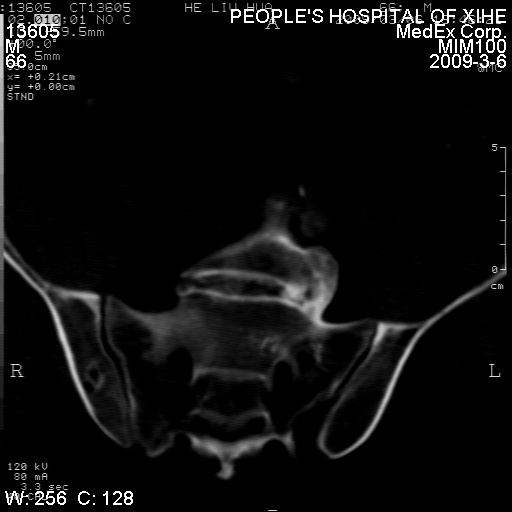

标题: CT18522:男,66岁。考虑结核有错吗 [打印本页]

标题: CT18522:男,66岁。考虑结核有错吗

x线片示:骶骨密度增高。

考虑----腰椎骶化-----退变-----椎管狭窄

腰骶椎退行性改变。

退行性变,椎体滑脱

腰椎滑脱并有退变

退行性变,椎体滑脱。建议同椎体平行进一步扫描。